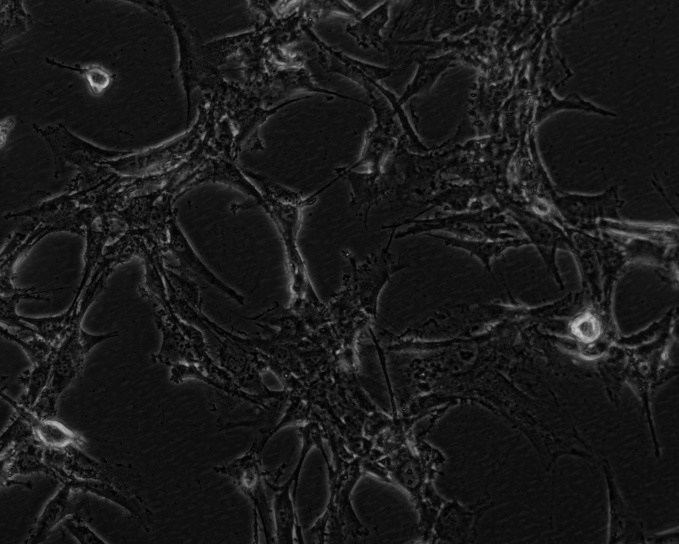

- 细胞类型:

胶质母细胞瘤;星形细胞瘤;2007级分类

贴壁

- 细胞形态:

上皮细胞样

- 物种来源:

大鼠

- 组织来源:

脑